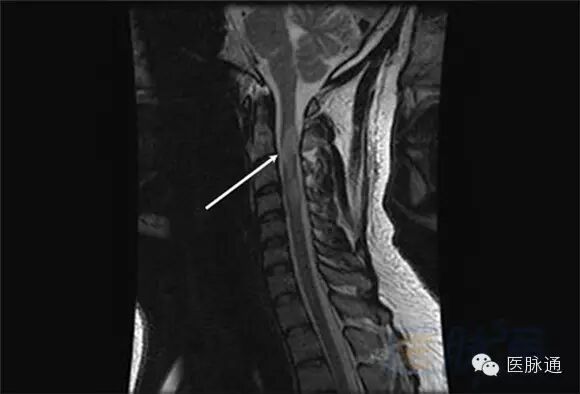

MRI对于评估脑干或脊髓病变也非常好。此处图像所示MS斑块在颈髓(箭头)。计算机断层扫描(CT)和超声对于MS的诊断作用非常有限。